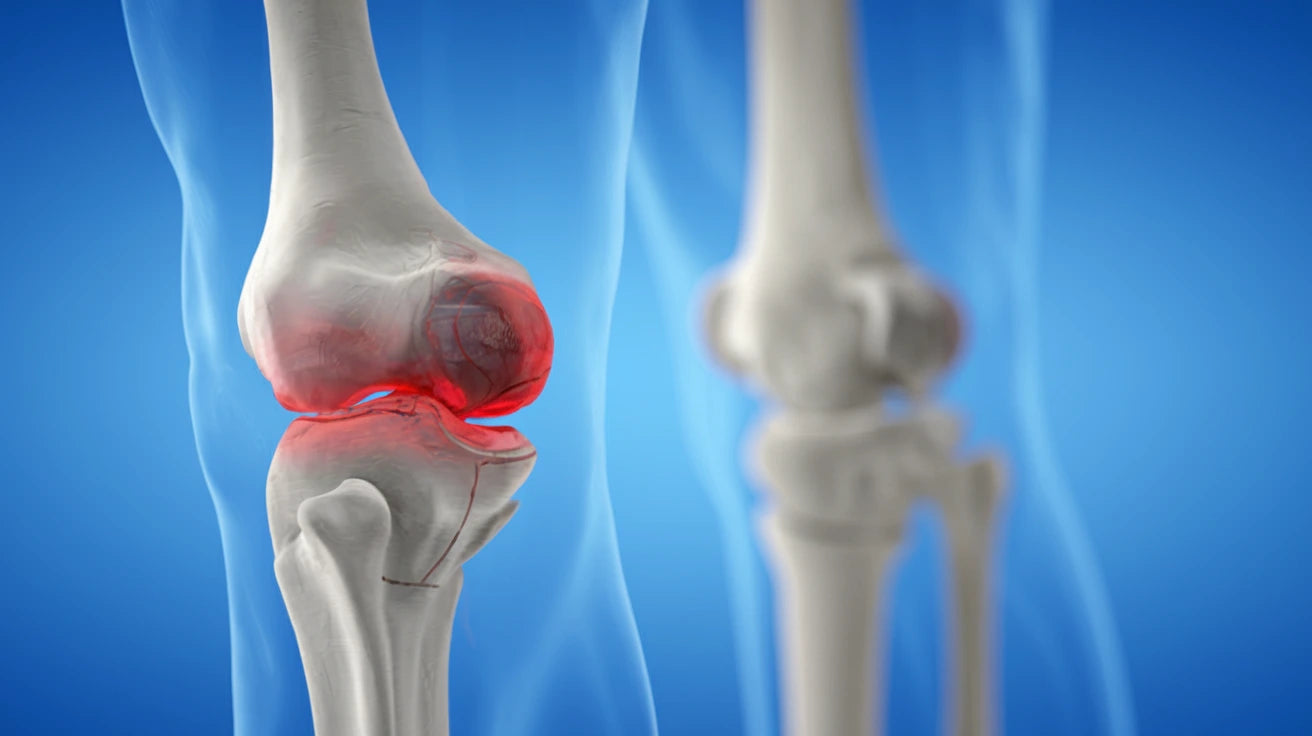

Knäleden är en av kroppens mest komplexa leder och utsätts dagligen för stor belastning. Knäproblem kan drabba personer i alla åldrar och uppstår av många olika orsaker.